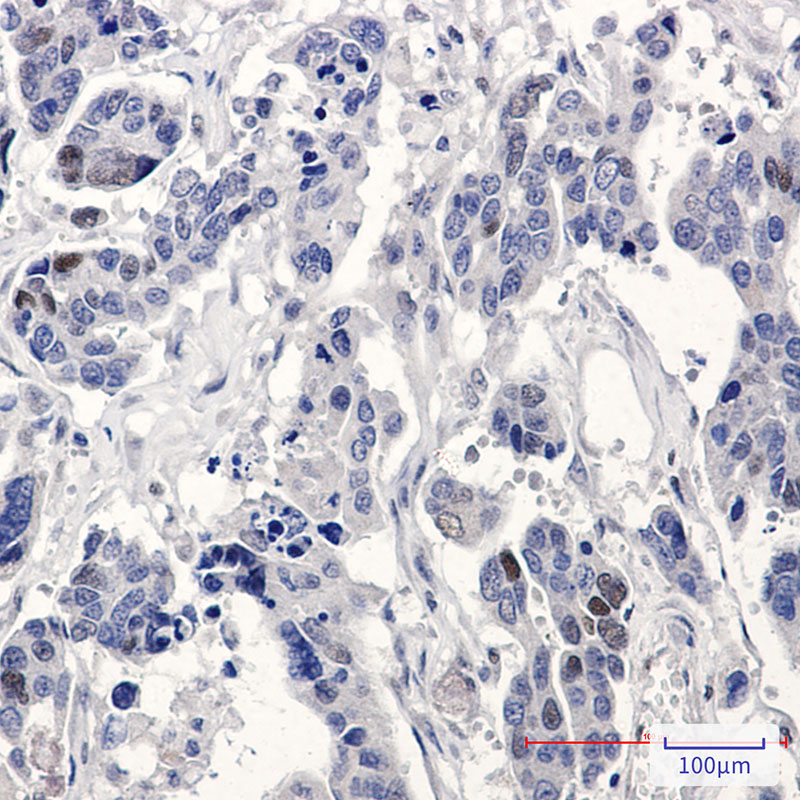

Product Image

| IHC | 1/50-1/100 |